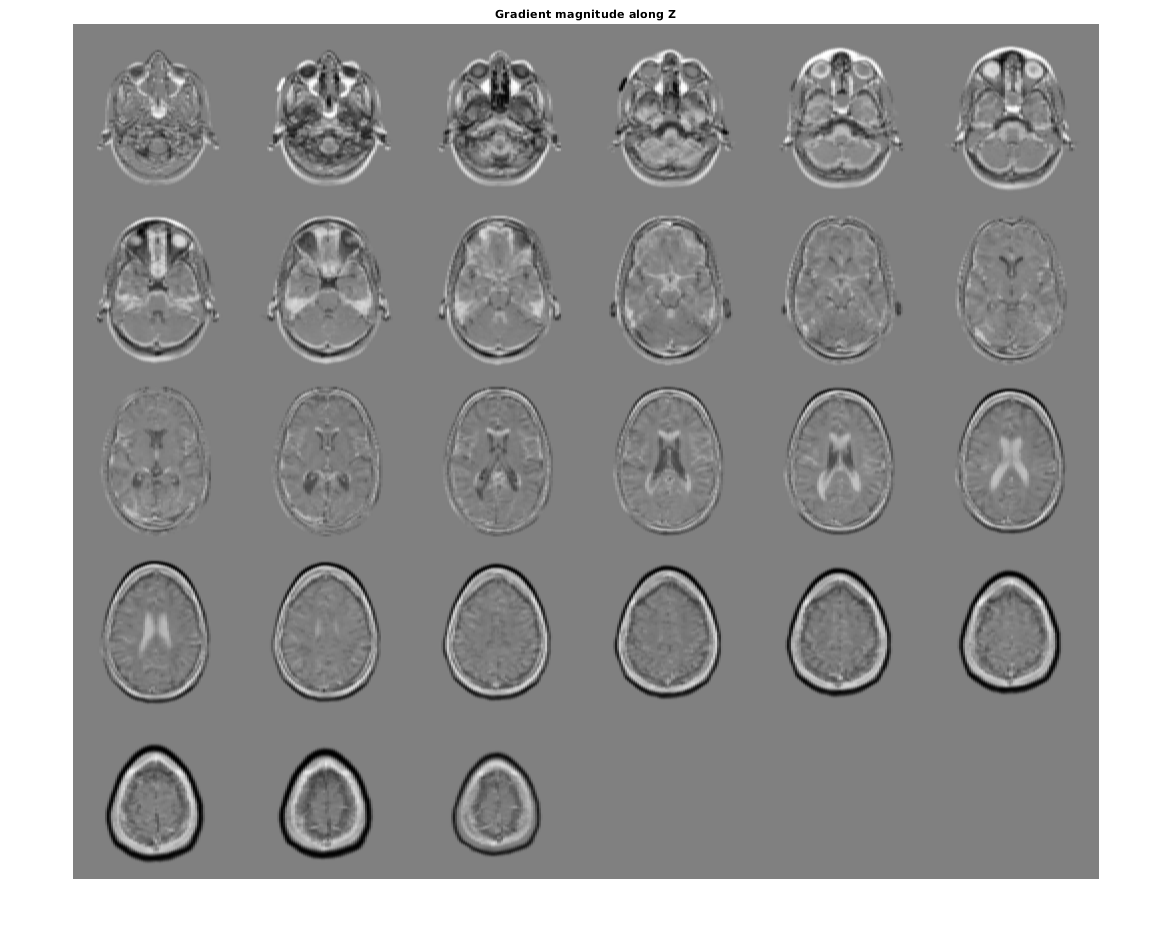

Визуализируйте направленные градиенты как монтаж.

figure, montage(reshape(Gx,sz(1),sz(2),1,sz(3)),'DisplayRange',[])

title('Gradient magnitude along X')

figure, montage(reshape(Gz,sz(1),sz(2),1,sz(3)),'DisplayRange',[])

title('Gradient magnitude along Z')